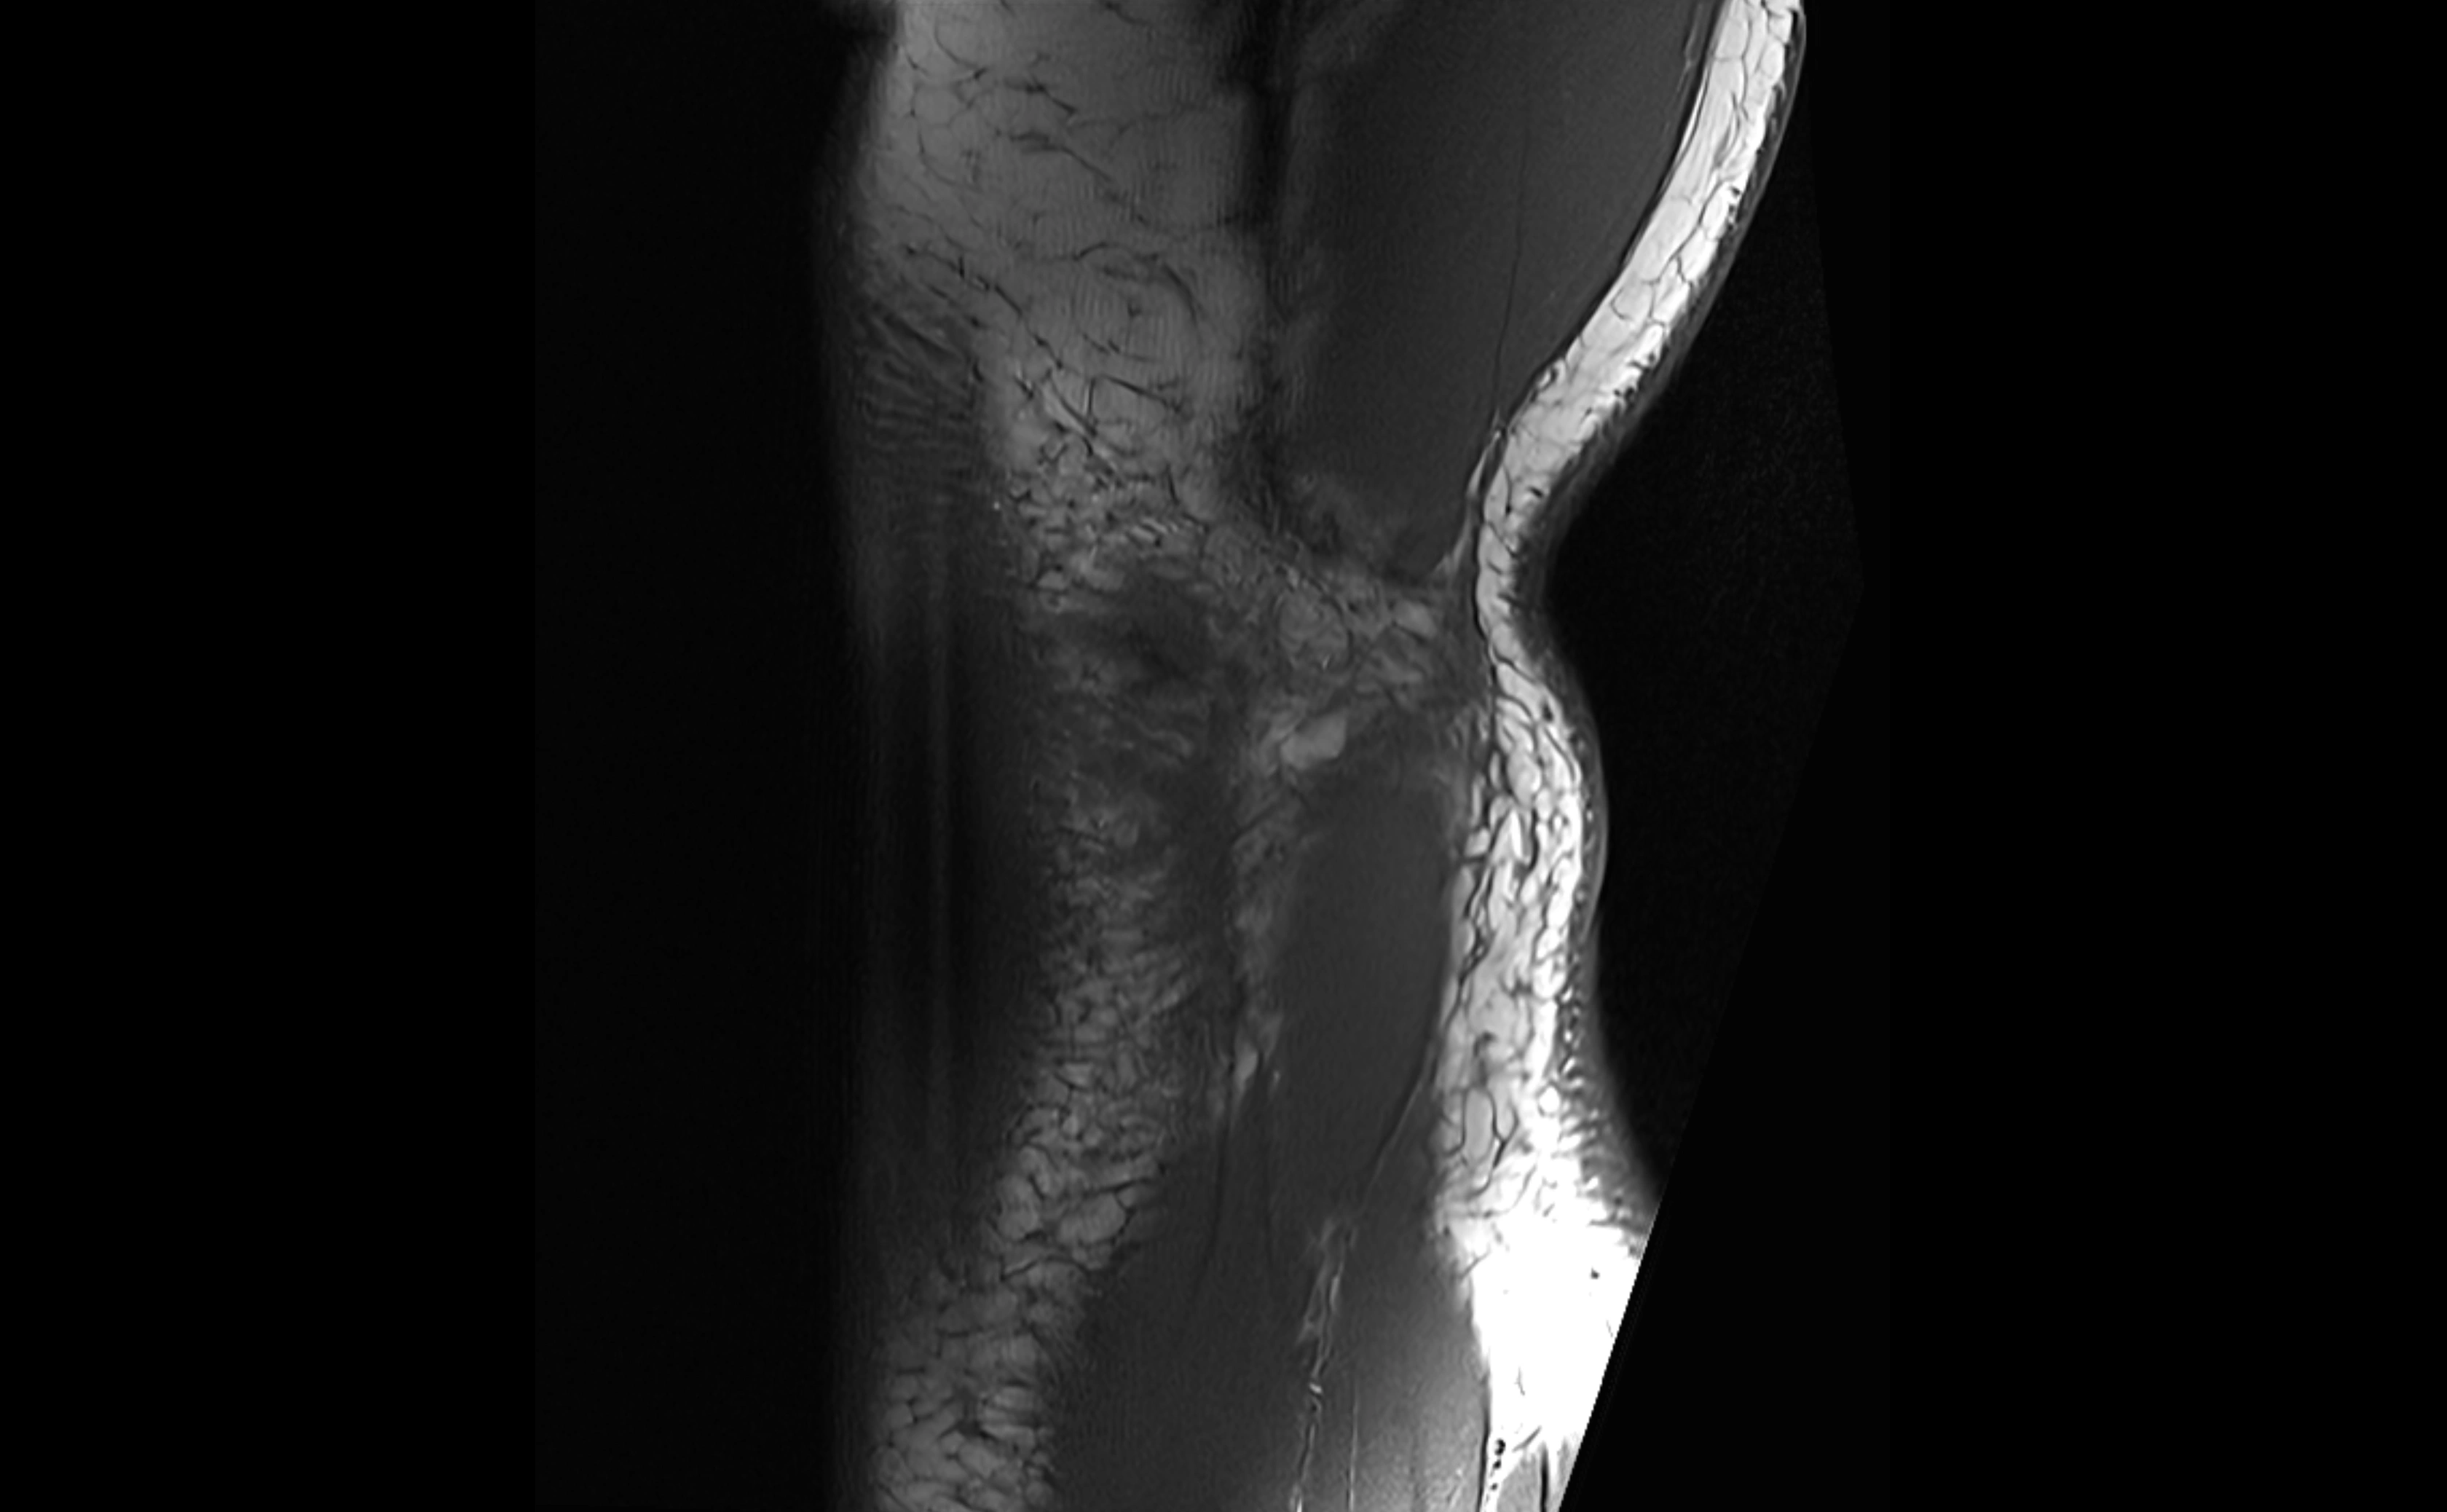

MRI images

image